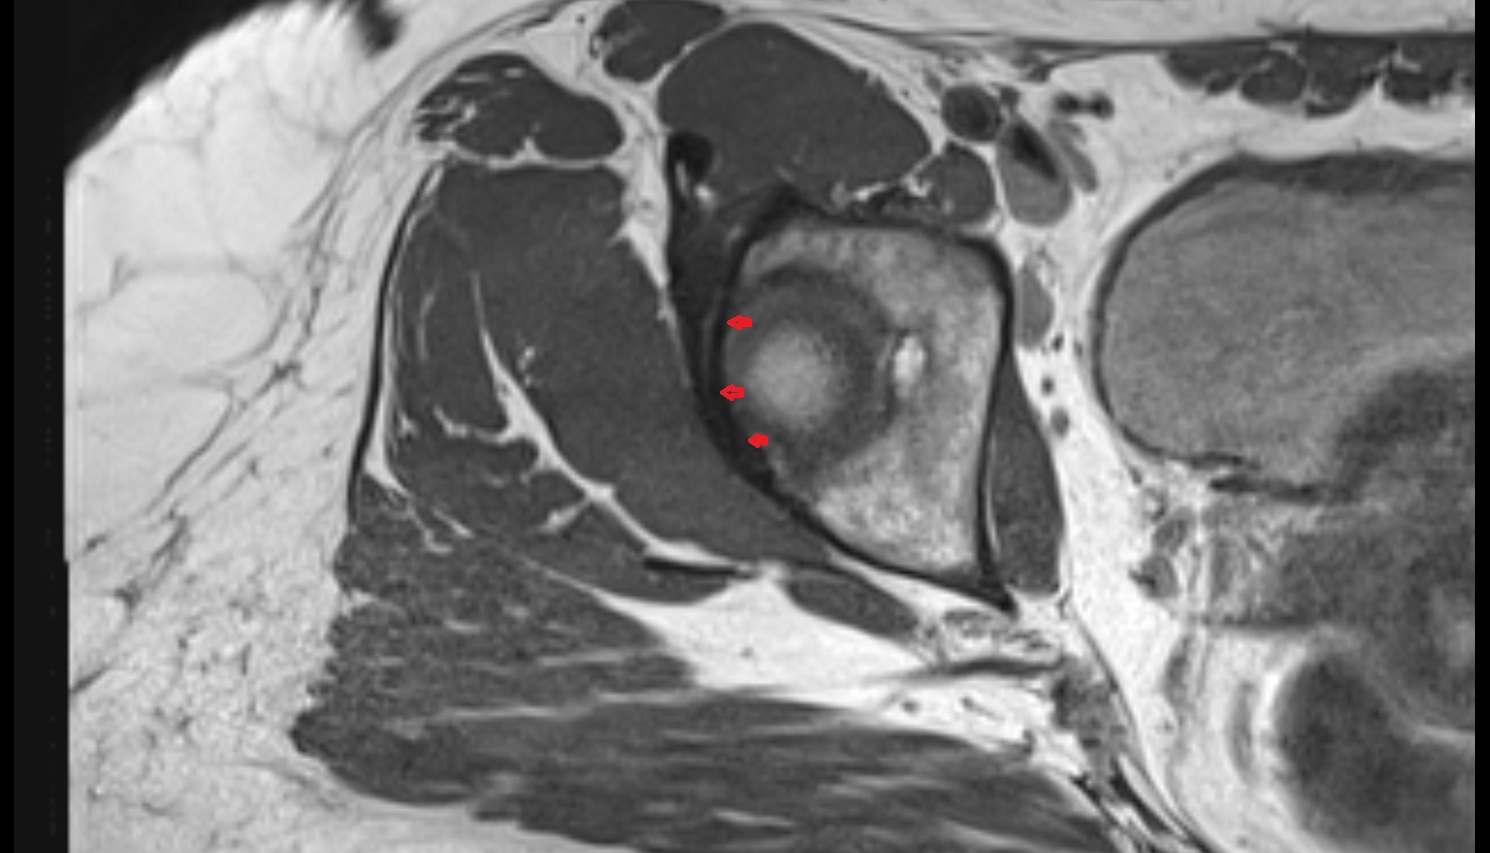

- Shoulder joint (glenohumeral joint)

- Glenoid labrum

- Supraspinatus tendon

- Infraspinatus tendon